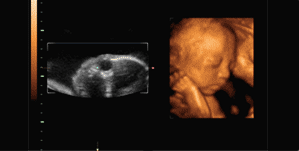

玛丽美国GE-S6四维彩超图像:

画质:立体动态成像,画质比较清晰

优势:在“二维”、“三维”的基础上,直观清晰地呈现胎儿在宫内的动态图像,多方位、多角度地观察孕宝宝的生长发育情况,还能够对孕妇潜藏的某些疾病进行检测,生育健康宝宝。

劣势:暂未发现

三维彩超图像:

画质:静态成像,画质模糊勉强辨识身体部位

优势:静态观察到附中胎儿的身体、器官等情况

劣势:图像以图片形式局部观察,清晰度较四维彩超稍差,检测不够完善

二维彩超图像:

画质:黑白静态成像

优势:静态剖面大致显示腹中胎儿的体表情况

劣势:图像不清晰且需专业人士讲解